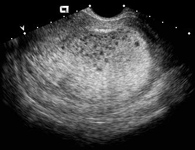

Molar Tissue Demonstrating Classical Snow Storm Appearance Seen To The

Molar tissue demonstrating classical snow storm appearance seen to the www.researchgate.net

molar pregnancy ultrasound snowstorm wikem findings

molar pregnancy ultrasound snow storm grapes uterus bunch scan